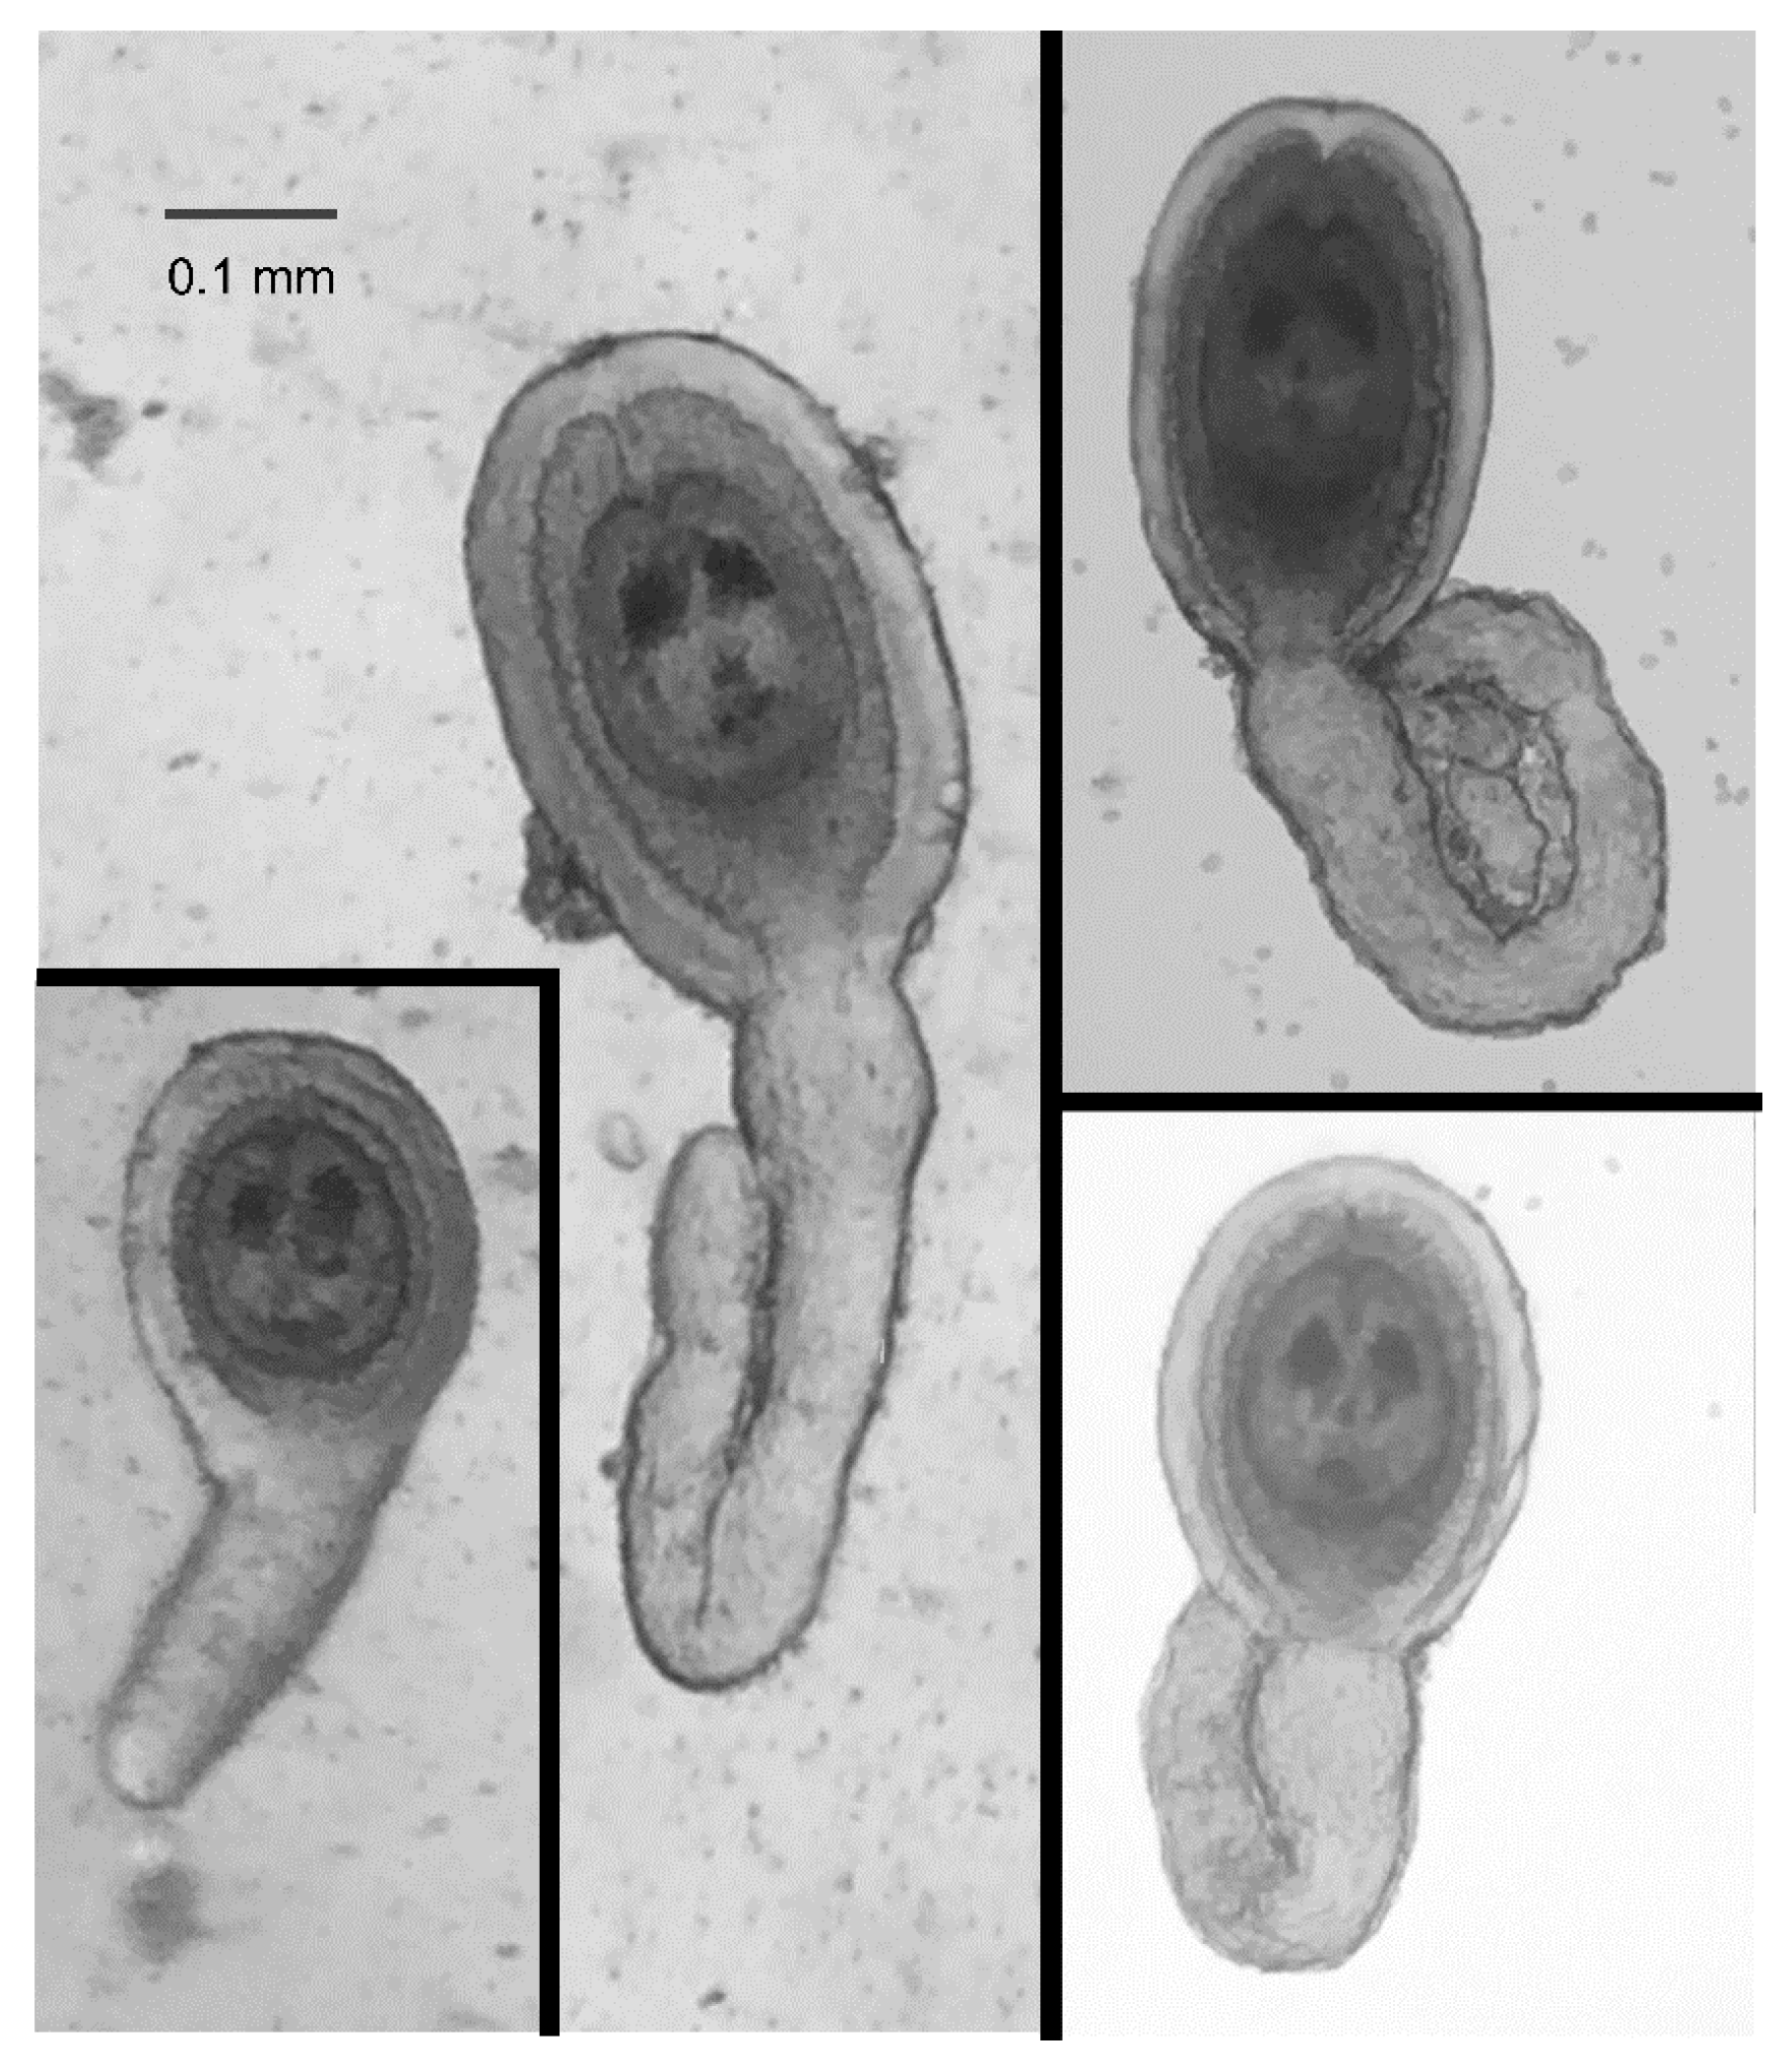

HDCs were readily identified based on their general shape, a disk-shaped and relatively opaque “head” surrounded by a gelatinous coating and attached to a relatively transparent “tail” of varying lengths (Figure 3). This general shape, however, could be naively mistaken for materials from the beetle were it not for the two characteristic “eye spots” in the head of the HDC (Figure 3). The size of the head, including the thickness of the jelly coating varied by a factor of between 2 and 3, but the majority of the variation in the morphology of the HDCs was exhibited in the tail length.

Figure 3.

Typical HDCs. HDCs vary in size over roughly a 5-fold range, and have substantial morphological variation in their “tail”. Photographs shown were taken using iPhone 6 cameras and either an OMAX dissecting microscope with a iDu LabCam Microscope Adapter for the iPhone (Left images) or a Wilovert inverted microscope (Right images) by two coauthors (CM and ZEH) working independently.